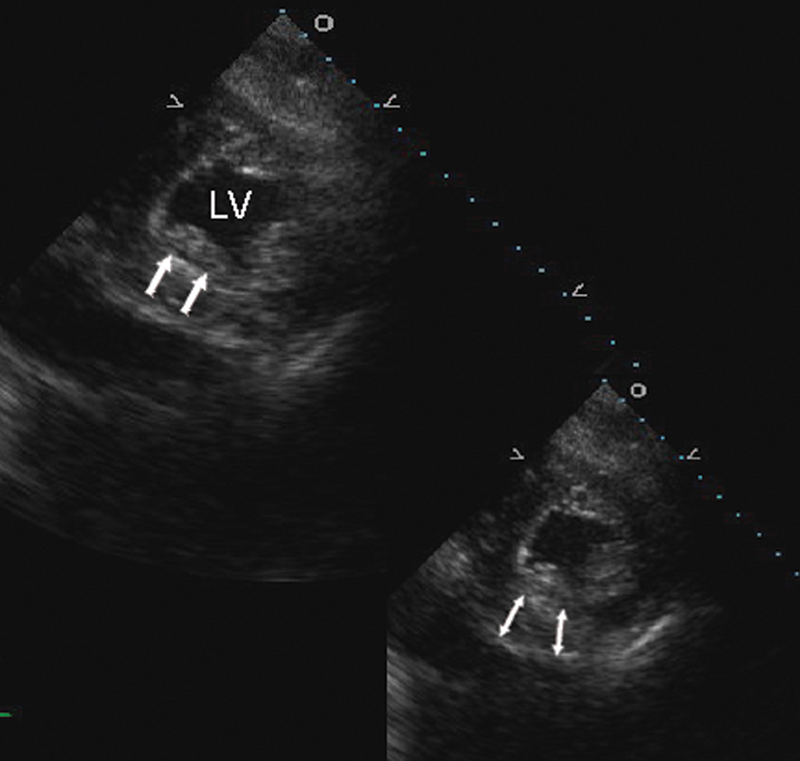

فحوصات تشخيصية لبعض امراض القلب والشرايين التاجية